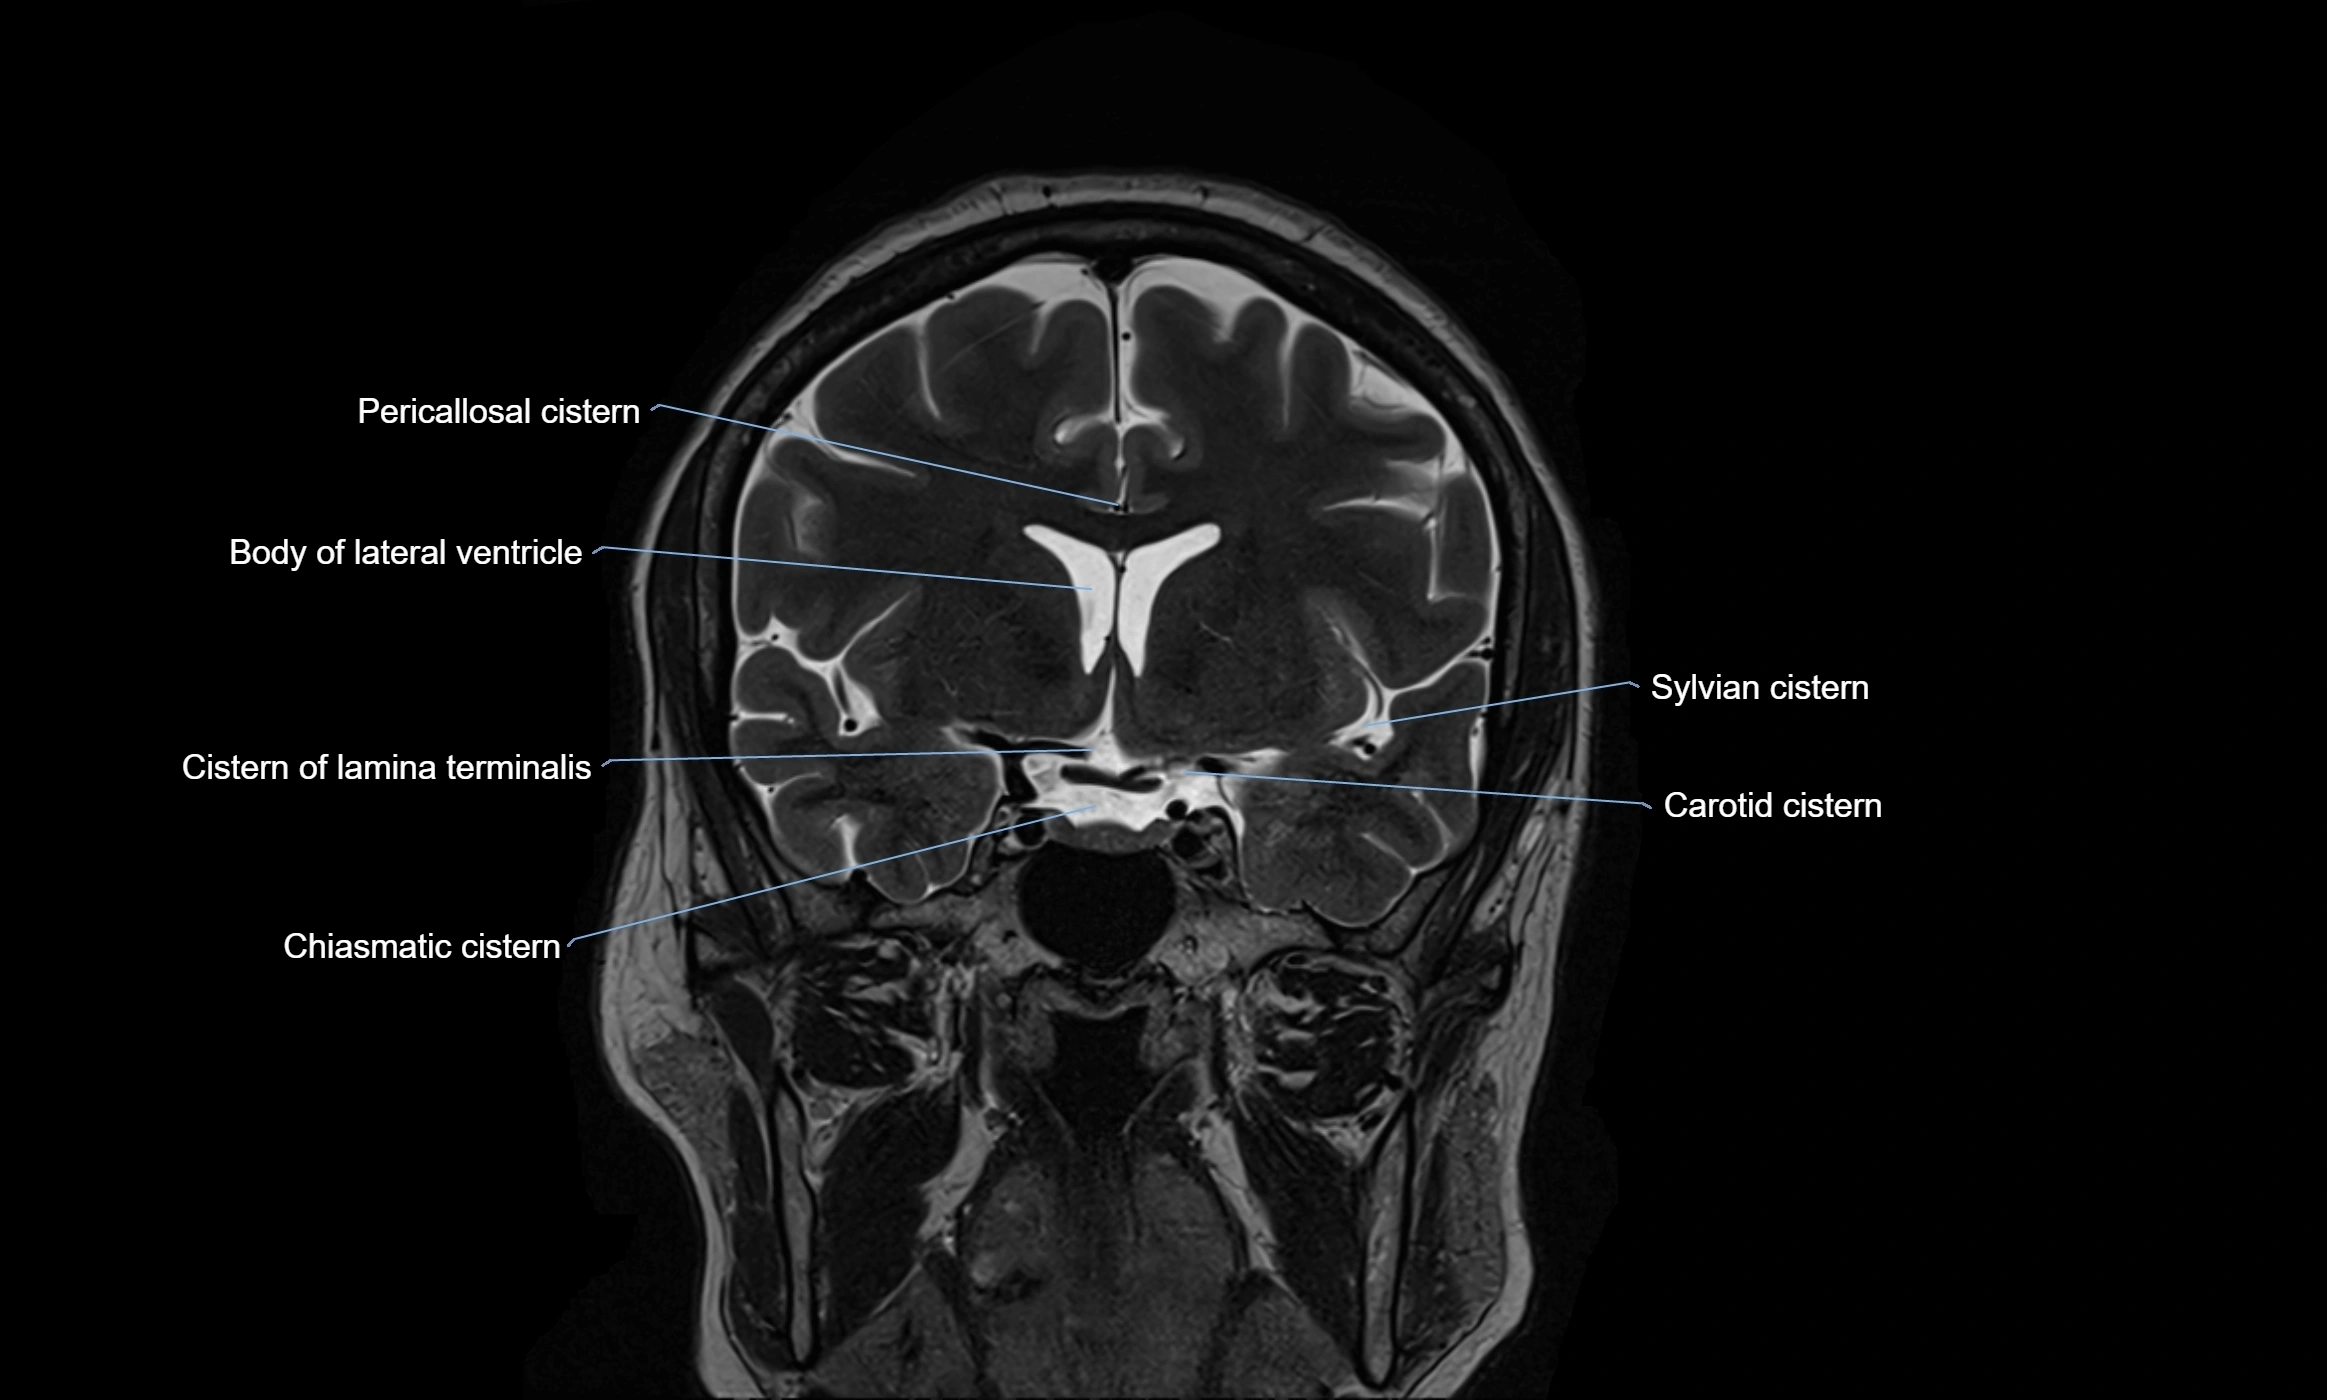

MRI images

image